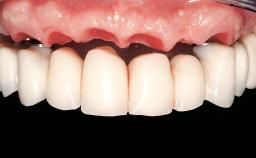

Immediate Loading of Six Implants in the Mandible and Six Implants in the Maxilla and Final Restoration with Full-Arch CAD/CAM Metal Framework FDPs Involving Digital Planning and Guided Surgery

Prosthesis Type FDP

Retention Screw-retained, with 4 or more splinted implants Screw-retained, with 4 or more splinted implants